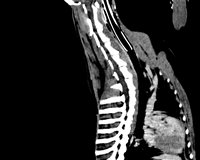

À partir des coupes natives axiales du patient, des logiciels de reconstruction permettent de faire des reformatages dans tous les autres plans (sagital, coronal ou oblique). Enfin, des reconstructions tridimensionnelles peuvent aussi être réalisées avec un rendu volumique, surfacique ou endoscopique.

Reconstructions 3D Corps entier avec rendu volumique